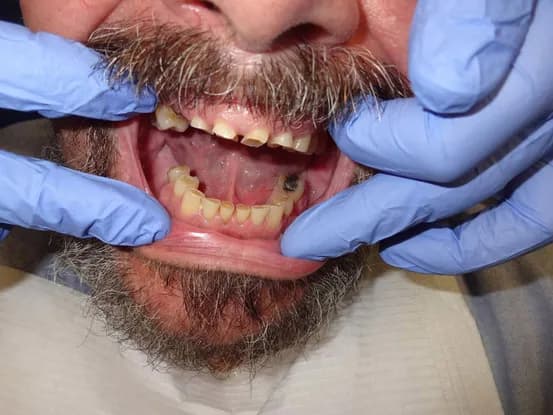

Case 2

64 year old male with severe grinding TMJ issues resulting in a 6 mm bite collapse. Root canals done on exposed teeth and full mouth rehabilitation with porcelain fused to metal crowns performed to restore proper form and function of dentition.